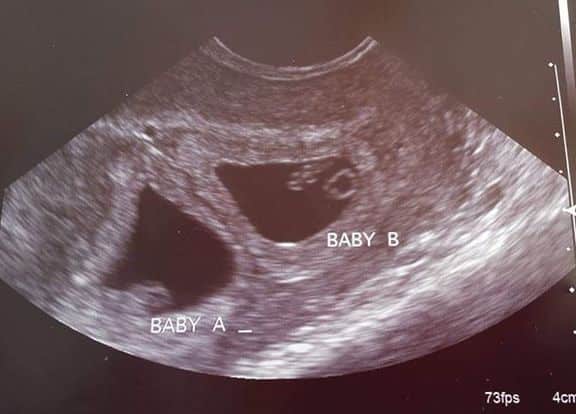

What Does an Ultrasound Look like at 6 Weeks Pregnant With Twins?

The earliest your doctor would likely order an ultrasound confirming twins would be 4 weeks pregnant. But unless you are going through fertility treatments, doing an ultrasound before 6 weeks isn’t very common, with the exception of complications. Women who are going through fertility treatments or have early complications may be able to have an early twin ultrasound at 4 or 5 weeks pregnant and find out they are pregnant with twins.

Yes! You’d need to have an ultrasound at 6 weeks to confirm a twin pregnancy. Your twin belly at 6 weeks may not look like much of a belly at all, so getting in to your doctor for an ultrasound is key to find out if you’re really having twins.